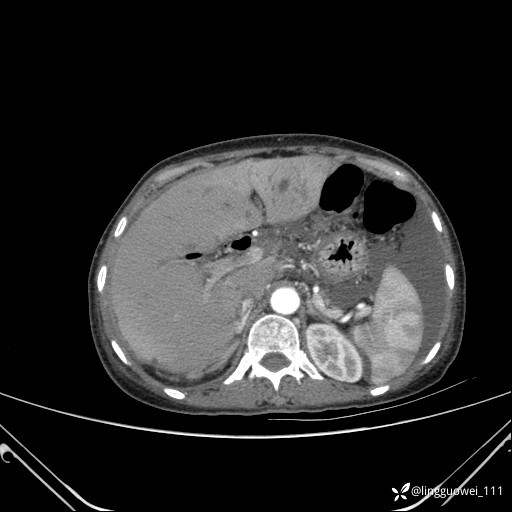

病例女,65岁,门诊行胃肠镜检查后,说腹胀入院检查,CT能发现病因吗?已公布结果

主诉:门诊行胃肠镜检查后,诉腹胀,入院检查,肝有病变吗?腹膜及腹腔的表现有特征性吗?

增强动脉期: